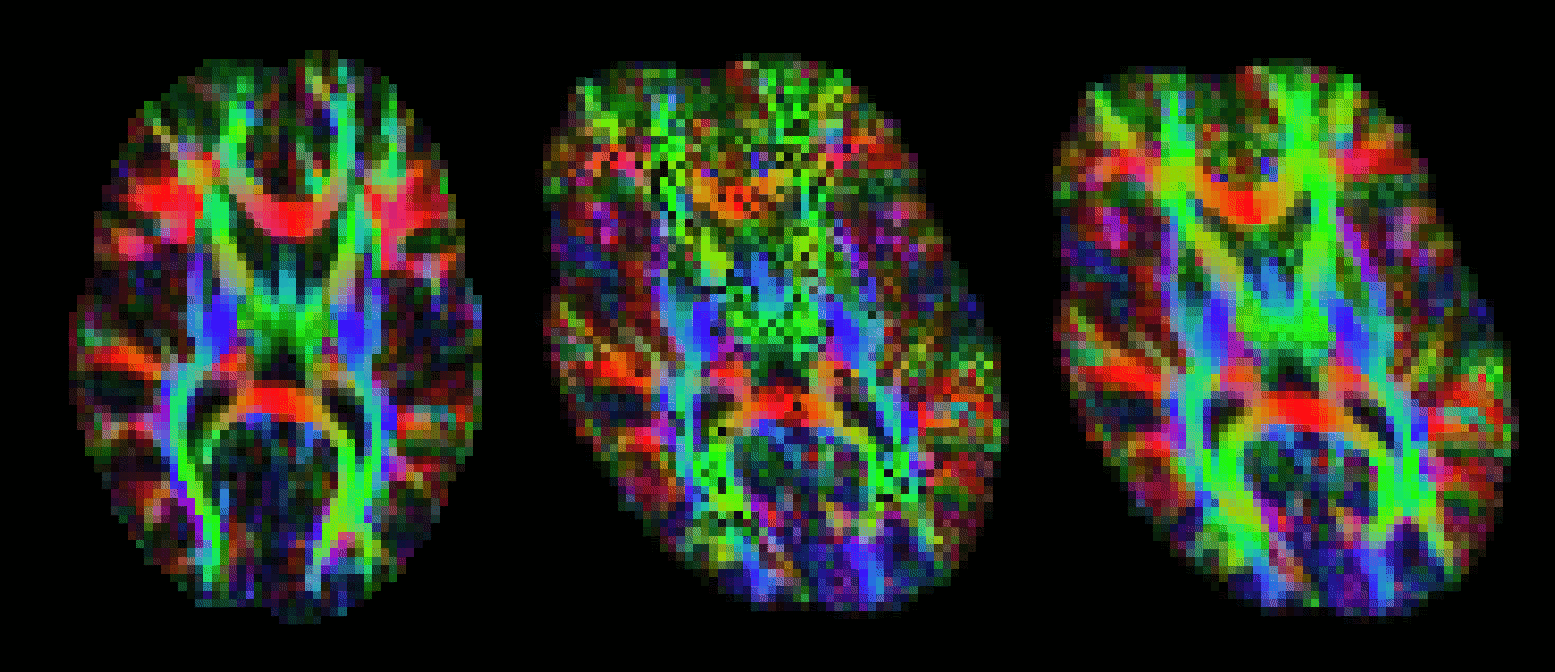

Outputs of bedpostx or dtifit can be conveniently displayed in fslview. If you open an image of diffusion vectors (e.g., dtifit_V1 output of dtifit or dyads<i> output of bedpostx) then it is possible to display these vectors using RGB coding (where the colours red,green and blue represent diffusion in the x,y,z axes respectively) or using lines where a line at each voxel represents the principle diffusion direction at that voxel.

It is also possible to display multiple lines per voxel. Each line will be displayed in a different colour. In the example above, the red lines represent the main fibre orientation, and the blue lines represent the secondary fibre orientations (thresholded at an f-value of 0.05), as calculated by bedpostx.

If you only want to visualise fibres within voxels where multiple fibres are supported (e.g. above a certain threshold for the corresponding mean_f<i>samples), then you first have to create a vector file where the voxels below a certain f-threshold are zeroed. You may use the two following command for that:

maskdyads dyads<i> mean_f<i>samples 0.05

For more details see the relevant fslview tutorial.